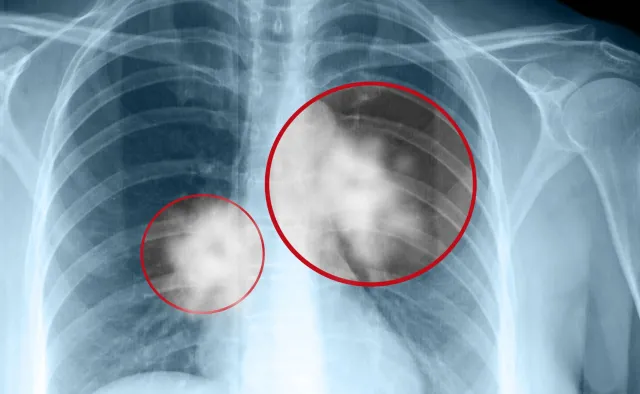

Zespół kierowany przez dr. Srirama Subramaniama wykorzystał mikroskopię krioelektronową (cryo-EM) do ujawnienia na poziomie atomowym struktury wrażliwego miejsca na białku kolca wirusa. Fragment ten określa się mianem epitopu. Jednocześnie naukowcy opisali przeciwciało VH Ab6, którego fragment jest zdolny do przyłączenia się do epitopu wirusa i jego całkowitej neutralizacji.

Takim uniwersalnym kluczem zidentyfikowanym w opisywanym badaniu okazał się fragment przeciwciała VH Ab6. Eksperymenty potwierdziły jego skuteczność przeciwko wariantom Alpha, Beta, Gamma, Delta, Kappa, Epsilon i Omicron. Fragment neutralizuje SARS-CoV-2 poprzez przyłączanie się do epitopu na białku kolca i blokowanie wirusa przed wnikaniem do ludzkich komórek.

„Epitop, który opisujemy w tej publikacji, nie jest objęty tzw. gorącymi punktami mutacji, dlatego jest zachowany w bardzo podobnej lub niezmienionej formie w różnych wariantach – mówi autor badania. - Teraz, gdy zdołaliśmy szczegółowo opisać jego strukturę, otworzyły się przed nami zupełnie nowe możliwości leczenia”.